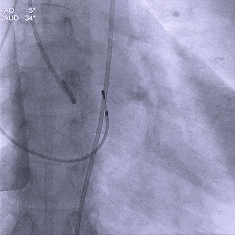

术中影像

根部造影:中大量反流,瓣叶活动度差

20mm球囊预扩:

轻微腰,无漏,左冠灌注正常